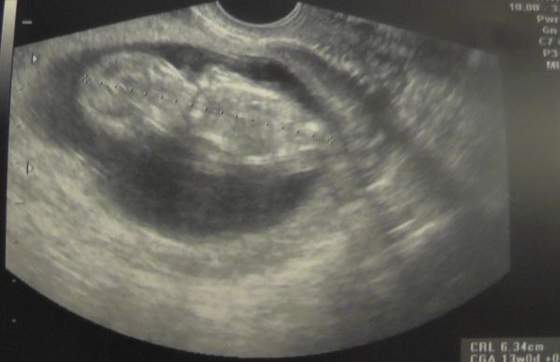

a to moje z wczoraj) 13t = 6,34

)